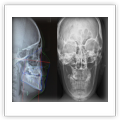

Telerradiografías de perfil

Telerradiofrafías de frente

Perfilograma de tejidos

duros y blandos